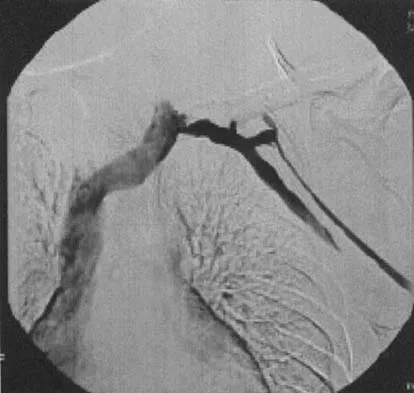

A well-developed college football player reports swelling and a heaviness in the arm after lifting weights. Examination reveals that distal pulses are normal and equal in both arms. A venogram is shown in Figure 13. What is the most likely cause of this condition?

Explanation

The clinical findings indicate venous obstruction without arterial compression, and the venogram reveals occlusion of the subclavian vein, which is most likely the result of thoracic outlet compression. In the developed athlete, scalene muscle hypertrophy (Paget-Schroetter syndrome) causes compression of the subclavian vein. Treatment should consist of thrombolysis followed by decompressive surgery. Angle N, Gelabert HA, Farooq MM, et al: Safety and efficacy of early surgical decompression of the thoracic outlet for Paget-Schroetter syndrome. Ann Vasc Surg 2001;15:37-42.

References:

- Azakie A, McElhinney DB, Thompson RW, et al: Surgical management of subclavian-vein effort thrombosis as a result of thoracic outlet compression. J Vasc Surg 1998;28:777-786.